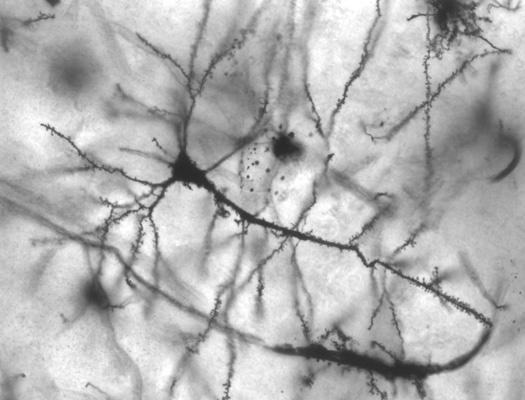

The electrodes used were non-penetrating, meaning they sit between the patient’s brain and skull, but do not actually poke into the brain. That means they are closer and more sensitive to specific brain waves than externally worn EEG caps, but are less invasive than penetrating electrodes. These electrodes can pick up on weak electrical signals within the brain, meaning they are more nuanced than other brain monitoring sensors and could possibly provide the technological sensitivity needed to get reliable thought-to-speech translation working.